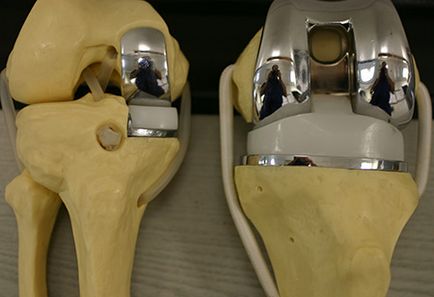

Duzzanat után csípőprotézis - ez az egyik lehetséges szövődmények, amely várhatóan azok számára, akik úgy döntött, a telepítés a protézis. Ilyen következmények elkerülése többféleképpen használható vérhígító, és a kopás speciális harisnya. Érzékelhető egészségre gyakorolt hatások és biztosítja gyógytorna. Terápiás masszázs is nem lesz felesleges.

Olvassa részletesebb cikket „térdprotézis” a honlapunkon.

A pusztítás az ízületi protézis struktúra az egyetlen módja, hogy helyreállítsa a mobilitás